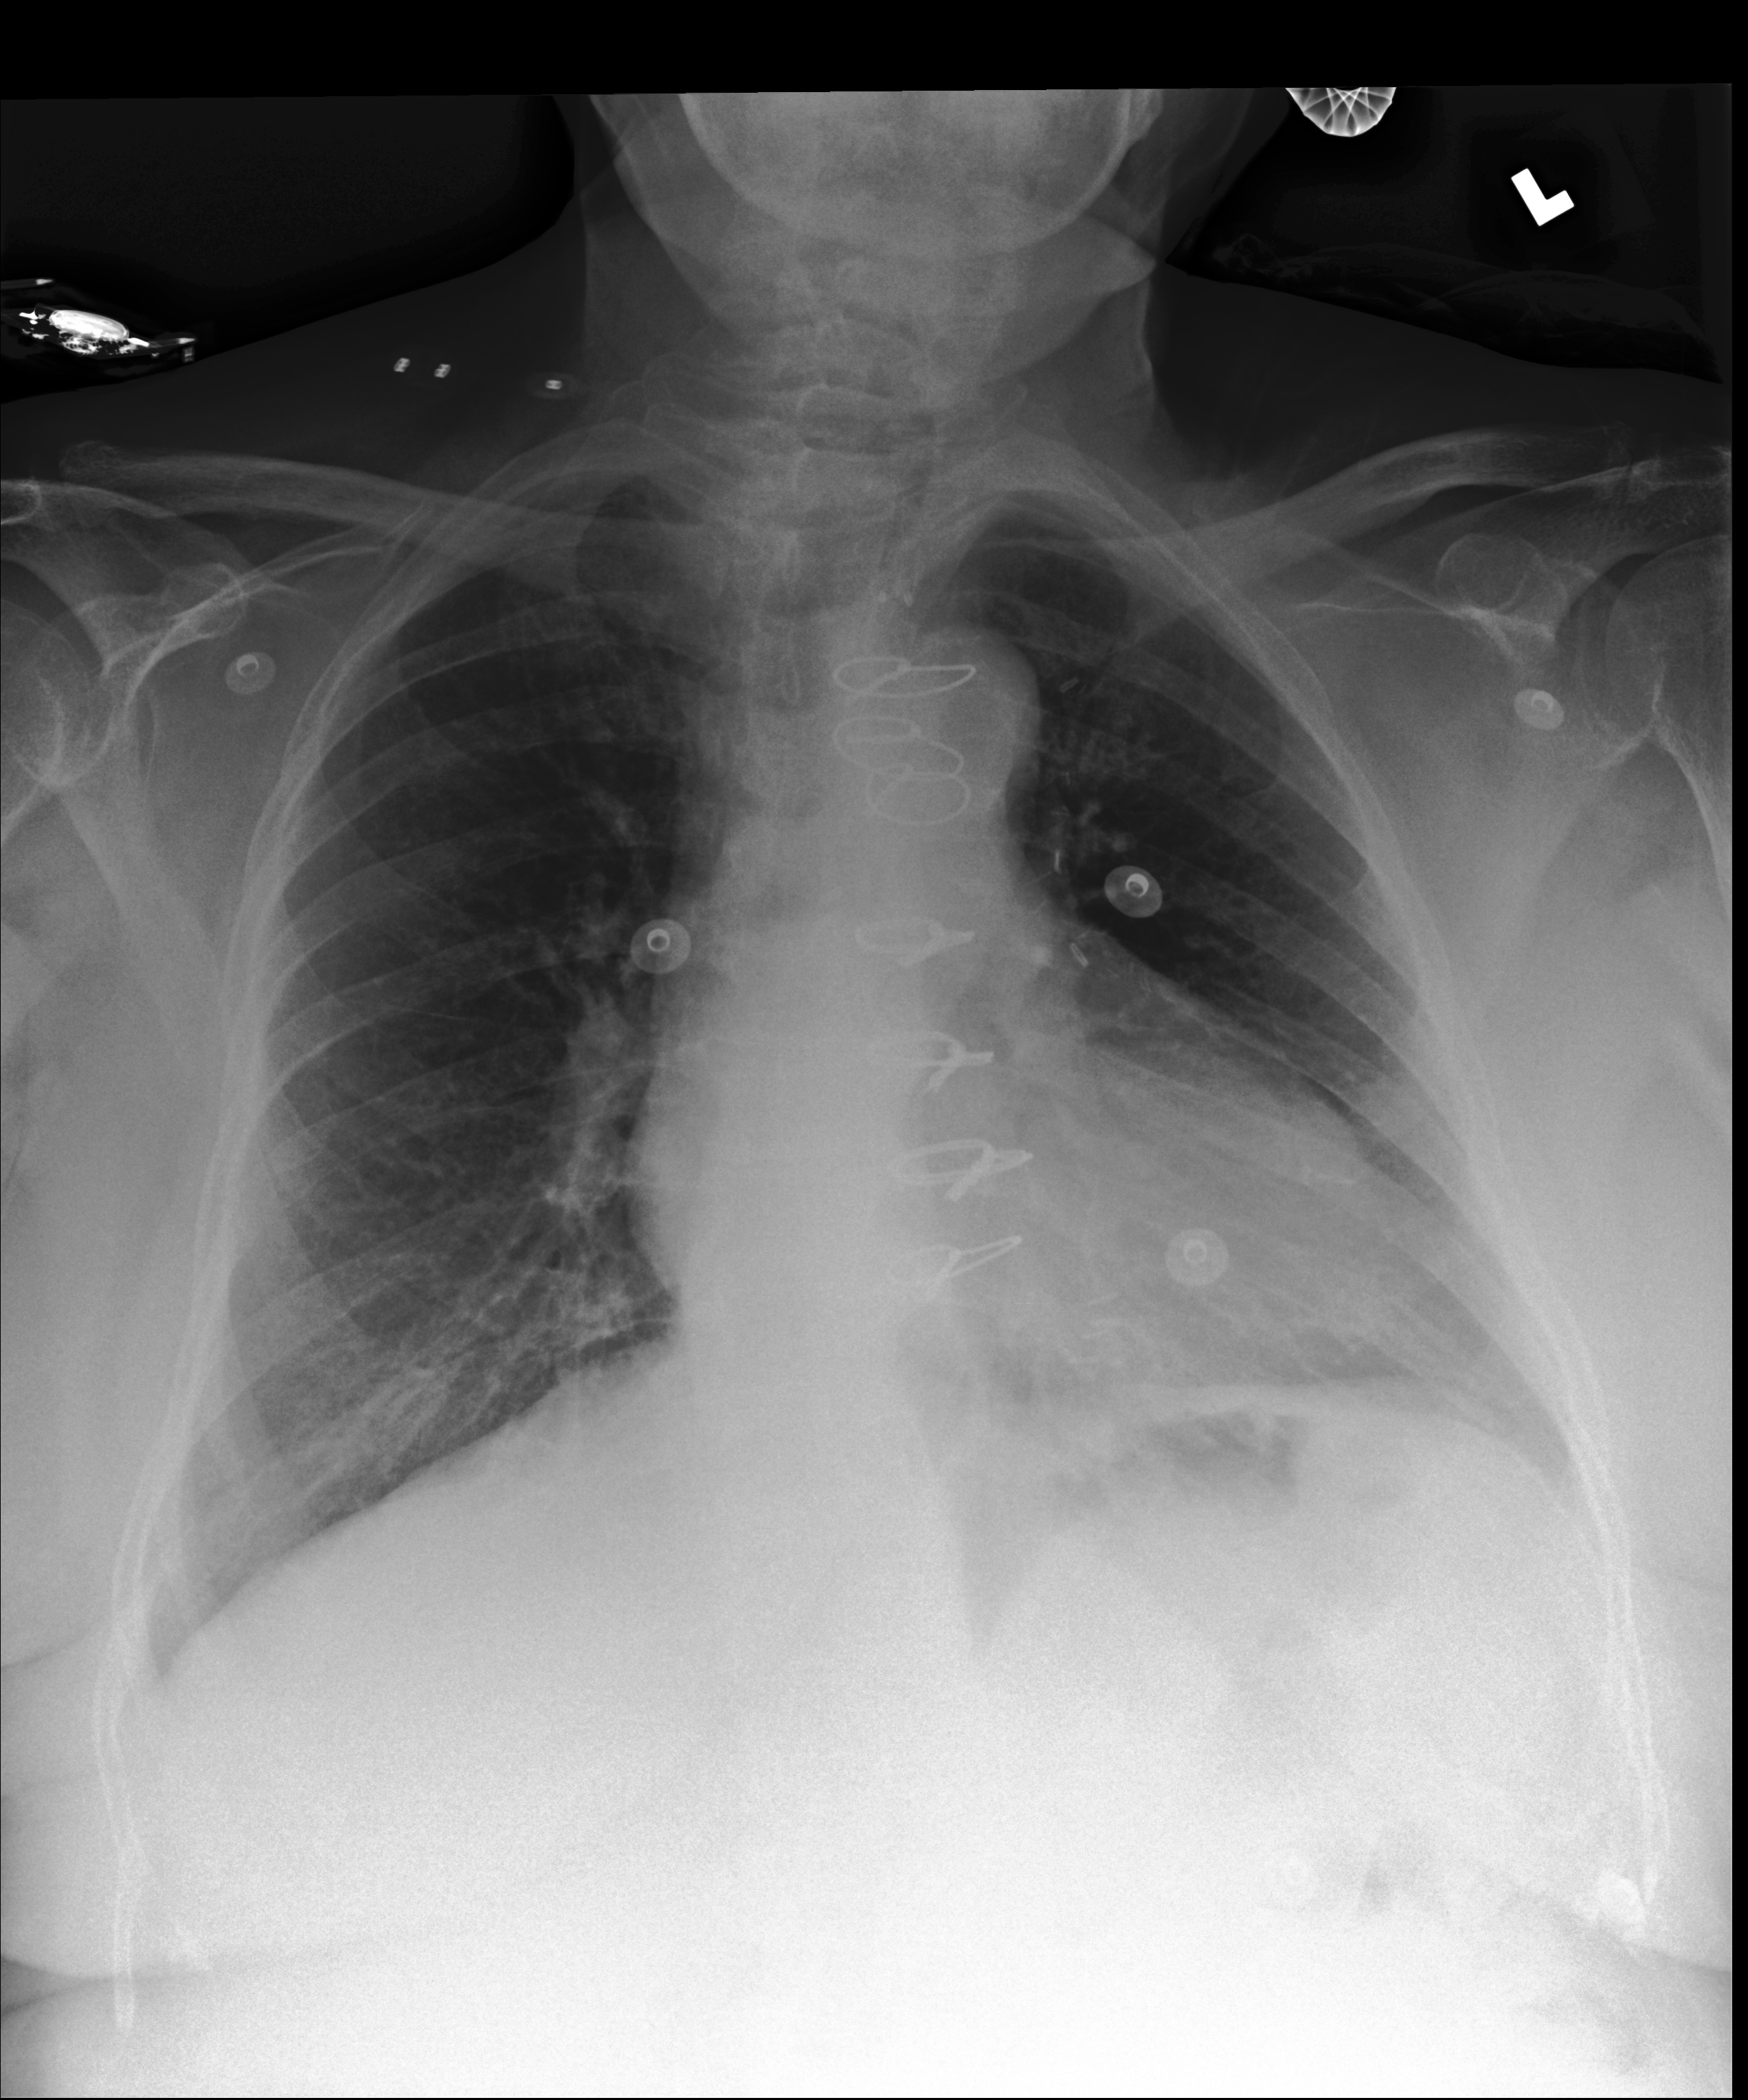

Example 1

[Uncaptioned image]

Generated

レントゲン写真を読影した結果、肺野に多数の小さな 白斑が見られます。これは肺炎の可能性があります。 心臓の形状は正常です。骨には異常は見られません。

(The X-ray examination shows multiple small white spots in the lung fields, which may indicate pneumonia. The shape of the heart is normal, and no abnormalities are observed in the bones.)

Ground truth

肺容量は低下している。左肺上葉と比較し、右上葉により強く瘢痕性、慢性の線維化が見られる。左肺中部に線状影が見られ、左下葉にも軽度見られる。胸水はない。心臓、縦郭の輪郭は正常である。

(The lung volume is reduced. Compared to the left upper lobe, the right upper lobe shows more pronounced scarring and chronic fibrosis. Linear opacities are observed in the mid-left lung, and mild findings are also present in the left lower lobe. There is no pleural effusion. The contours of the heart and mediastinum are normal.)